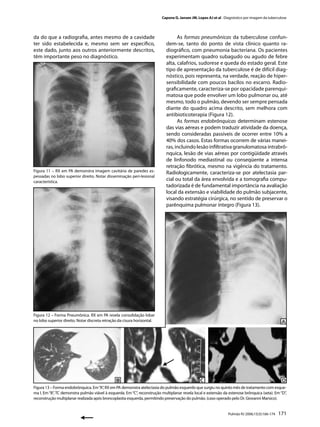

da do que a radiografia, antes mesmo de a cavidade                                  As formas pneumônicas da tuberculose confun-

ter sido estabelecida e, mesmo sem ser específico,                            dem-se, tanto do ponto de vista clínico quanto ra-

este dado, junto aos outros anteriormente descritos,                         diográfico, com pneumonia bacteriana. Os pacientes

têm importante peso no diagnóstico.                                          experimentam quadro subagudo ou agudo de febre

alta, calafrios, sudorese e queda do estado geral. Este

tipo de apresentação da tuberculose é de difícil diag-

nóstico, pois representa, na verdade, reação de hiper-

sensibilidade com poucos bacilos no escarro. Radio-

graficamente, caracteriza-se por opacidade parenqui-

matosa que pode envolver um lobo pulmonar ou, até

mesmo, todo o pulmão, devendo ser sempre pensada

diante do quadro acima descrito, sem melhora com

antibioticoterapia (Figura 12).

As formas endobrônquicas determinam estenose

das vias aéreas e podem traduzir atividade da doença,

sendo consideradas passíveis de ocorrer entre 10% a

40% dos casos. Estas formas ocorrem de várias manei-

ras, incluindo lesão infiltrativa granulomatosa intrabrô-

nquica, lesão de vias aéreas por contigüidade através

de linfonodo mediastinal ou conseqüente a intensa

retração fibrótica, mesmo na vigência do tratamento.

Figura 11 – RX em PA demonstra imagem cavitária de paredes es-               Radiologicamente, caracteriza-se por atelectasia par-

pessadas no lobo superior direito. Notar disseminação peri-lesional

característica.

cial ou total da área envolvida e a tomografia compu-

tadorizada é de fundamental importância na avaliação

local da extensão e viabilidade do pulmão subjacente,

visando estratégia cirúrgica, no sentido de preservar o

parênquima pulmonar íntegro (Figura 13).

Figura 12 – Forma Pneumônica. RX em PA revela consolidação lobar

no lobo superior direito. Notar discreta retração da cisura horizontal.

Figura 13 – Forma endobrônquica. Em “A”, RX em PA demonstra atelectasia do pulmão esquerdo que surgiu no quinto mês de tratamento com esque-

ma I. Em “B”, TC demonstra pulmão viável à esquerda. Em “C”, reconstrução multiplanar revela local e extensão da estenose brônquica (seta). Em “D”,

reconstrução multiplanar realizada após broncoplastia esquerda, permitindo preservação do pulmão. (caso operado pelo Dr. Giovanni Marsico).